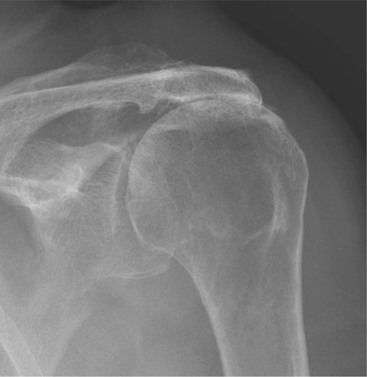

Radiography is useful for demonstrating bony abnormalities of the AC joint and acromion and excluding associated GHJ arthrosis (Fig. 46-1). Marked narrowing of the subacromial space is a specific but insensitive sign of a full thickness rotator cuff tear3 (Fig. 46-2). MRI and ultrasound (US) directly visualise the rotator cuff tendons. Both techniques are capable of diagnosing tendinopathy (Fig. 46-3), and have nearly 100% accuracy rates for FTTs of the rotator cuff.4 MR arthrography is not usually indicated for primary rotator cuff disease. The most important features to describe that help determine management include the following: